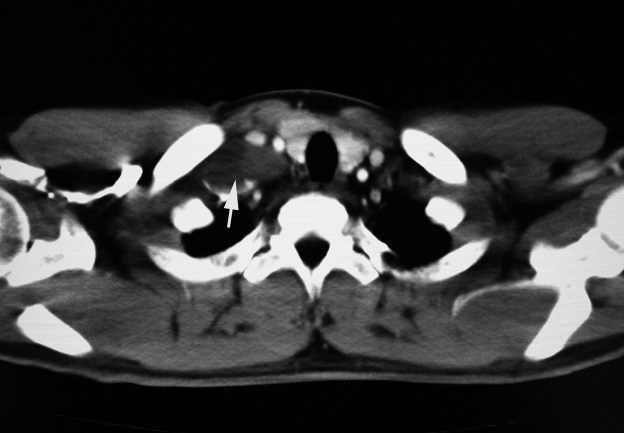

31歳男性 胸腺・頸部腫瘤

頸部の腫瘤に気づく. 次第に大きくなり受診。頸部腫瘤以外に, 発熱など症状はない。 CTで胸腺に最大の腫瘤が認められ、鎖骨上窩、頸部リンパ節腫大が認められた。肝・脾腫なし。腹部腫瘤は認められない。LDH 192IU/L, sIL-2R 5515 高値。